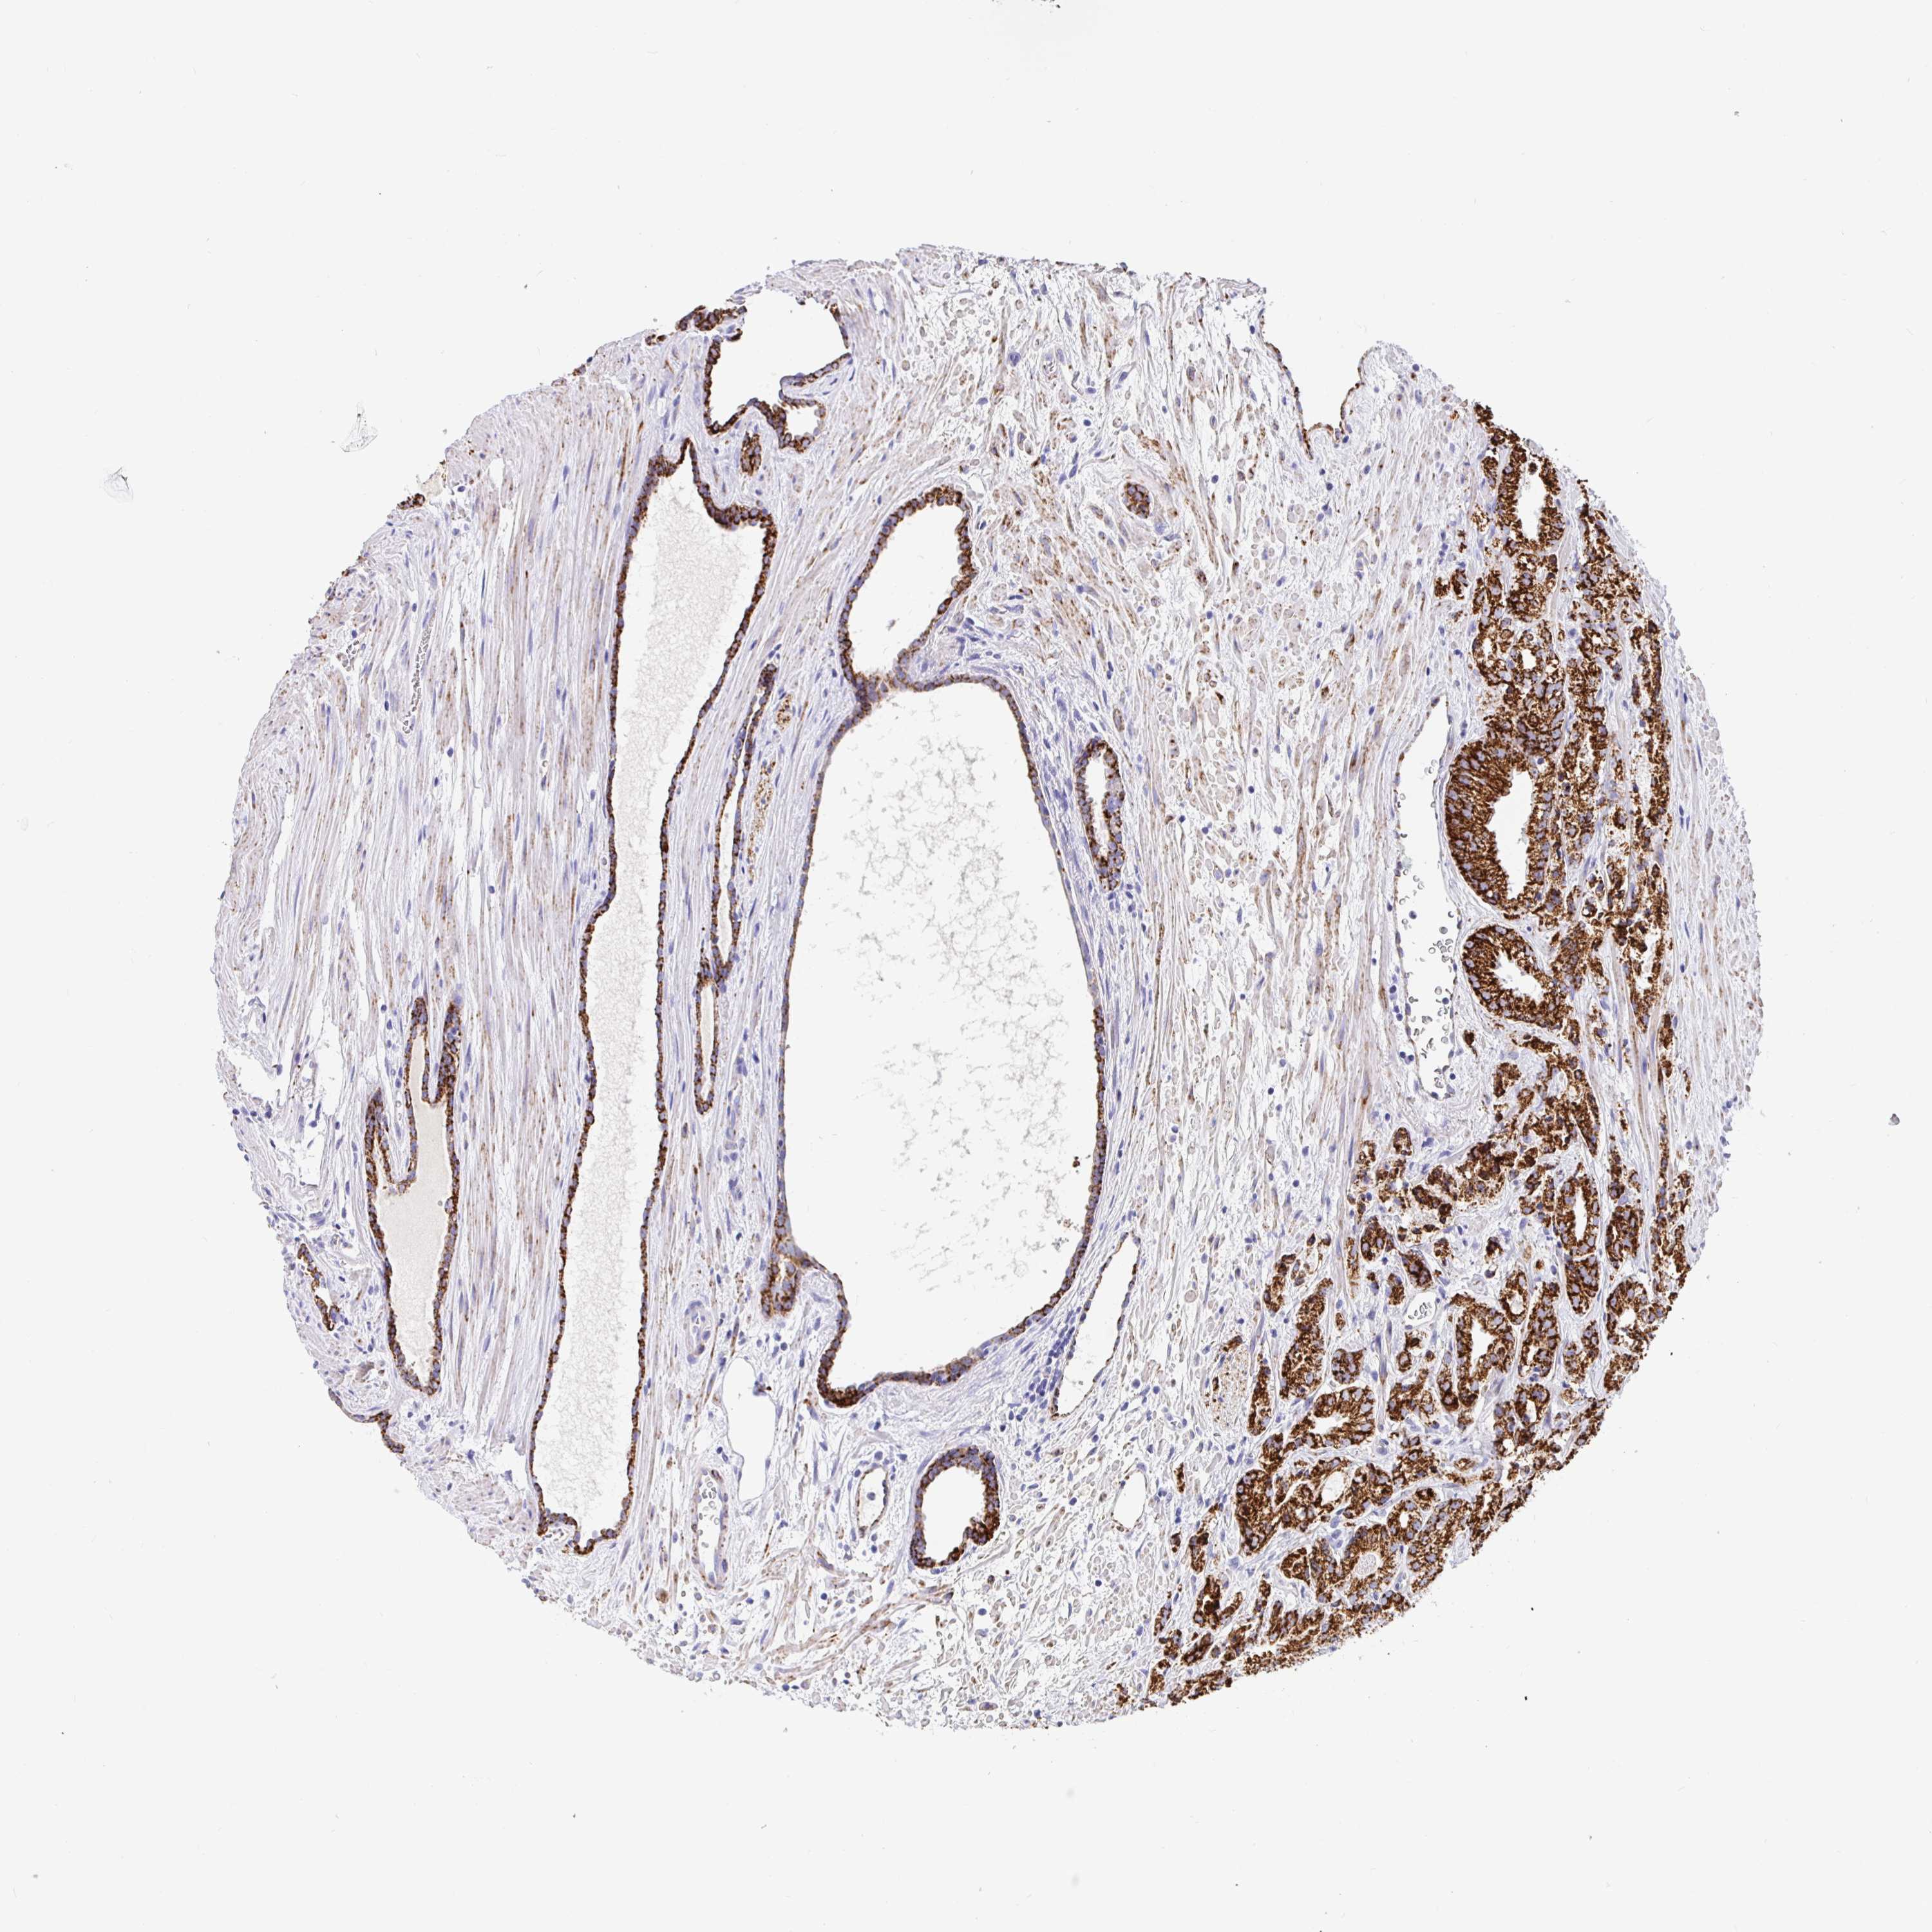

PROSTATE CANCER - Protein expressioni

A mouse-over function shows sample information and annotation data. Click on an image to view it in a full screen mode. Samples can be filtered based on level of antibody staining by selecting one or several of the following categories: high, medium, low and not detected. The assay and annotation is described here.

Note that samples used for immunohistochemistry by the Human Protein Atlas do not correspond to samples in the TCGA dataset.

Antibody stainingi

Antibody staining in the annotated cell types in the current human tissue is reported as not detected, low, medium, or high, based on conventional immunohistochemistry profiling in selected tissues. This score is based on the combination of the staining intensity and fraction of stained cells.

Each image is clickable and will lead to virtual microscopy that enables deeper exploration of all samples and also displays staining intensity scores, fraction scores and subcellular localization as well as patient and tissue information for each sample.

Antibody HPA054807

Antibody HPA059299

Antibody CAB009437

Staining

High

Medium

Low

Not detected

Intensity

Strong

Moderate

Weak

Negative

Quantity

>75%

75%-25%

<25%

None

Location

Nuclear

Cytoplasmic/membranous

Cytoplasmic/membranous,nuclear

Adenocarcinoma, High grade

Adenocarcinoma, Medium grade

Adenocarcinoma, Low grade